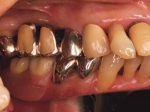

両側5歯症例 主訴-義歯のバネが壊れて手前の歯が痛んできた。 術前(旧義歯装着、鏡像)

術前口腔内(正面観)